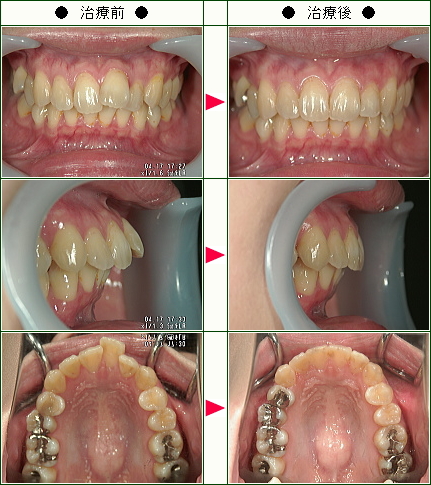

☆歯のデコボコ矯正症例(M・K様 26歳 女性)